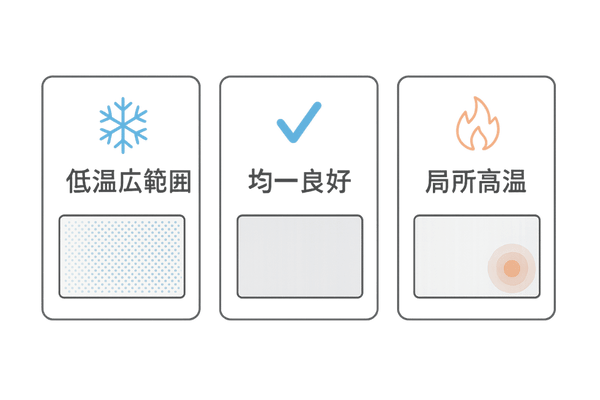

| 温度状態 | 考えられる頭皮の状態 | 髪への影響 |

|---|---|---|

| 全体的に青・緑(低温) | 広範囲な血行不良、冷え | 髪の成長が遅くなる、細くなる |

| 全体的に赤・黄(均一) | 良好な血行状態 | 髪が健やかに成長しやすい |

| 局所的に赤・黄(高温) | 炎症、かゆみ、皮脂の過剰分泌 | 頭皮環境の悪化、抜け毛の原因 |